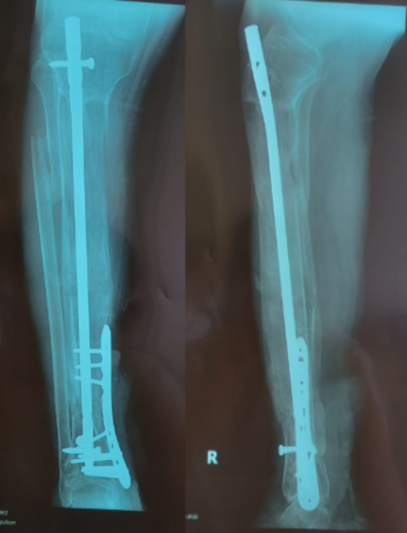

Tras un accidente de tránsito, Yessenia presentó una fractura expuesta con un defecto óseo de 10 cm en su pierna. Había recibido tratamientos previos sin éxito y su movilidad estaba en riesgo.

Con la técnica de osteogénesis por distracción y el uso de un tutor circular Ilizarov, se inició un proceso de regeneración ósea progresiva, acompañado de un seguimiento cercano.

Hoy Yessenia evoluciona favorablemente, conserva movilidad en su rodilla y tobillo, y está recuperando la independencia que pensaba perdida.